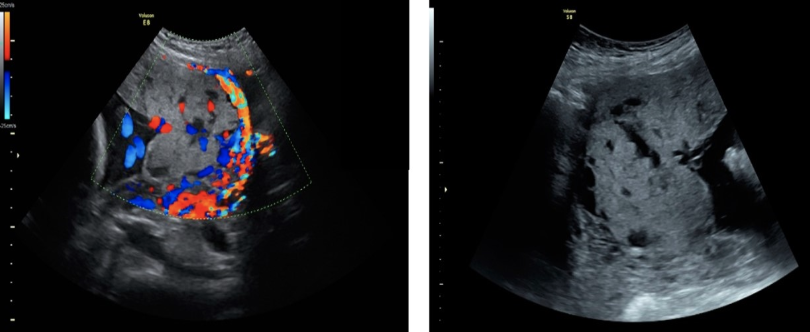

which shows as hypoechoic areas within the placenta that display turbulent flow on color doppler

.

a) infarction

b) placenta accreta

c) fibrin deposition

d) venous lake